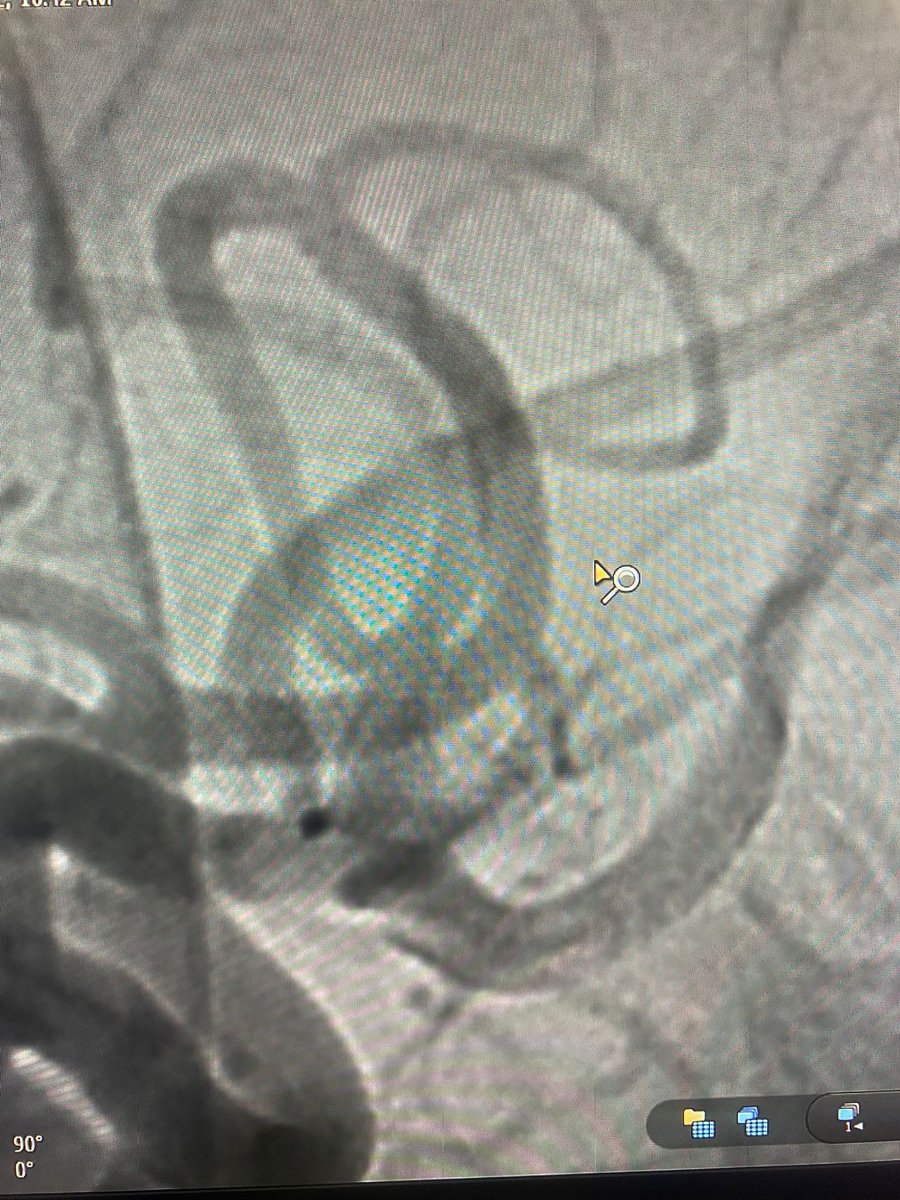

El Dr. Carlos Pérez@Justcharly9, nos resume en menos de 15 minutos los dos principales ensayos clínicos que comparan tratamiento Endovascular VS Quirúrgico (ISAT, IBRAT) de aneurismas rotos.